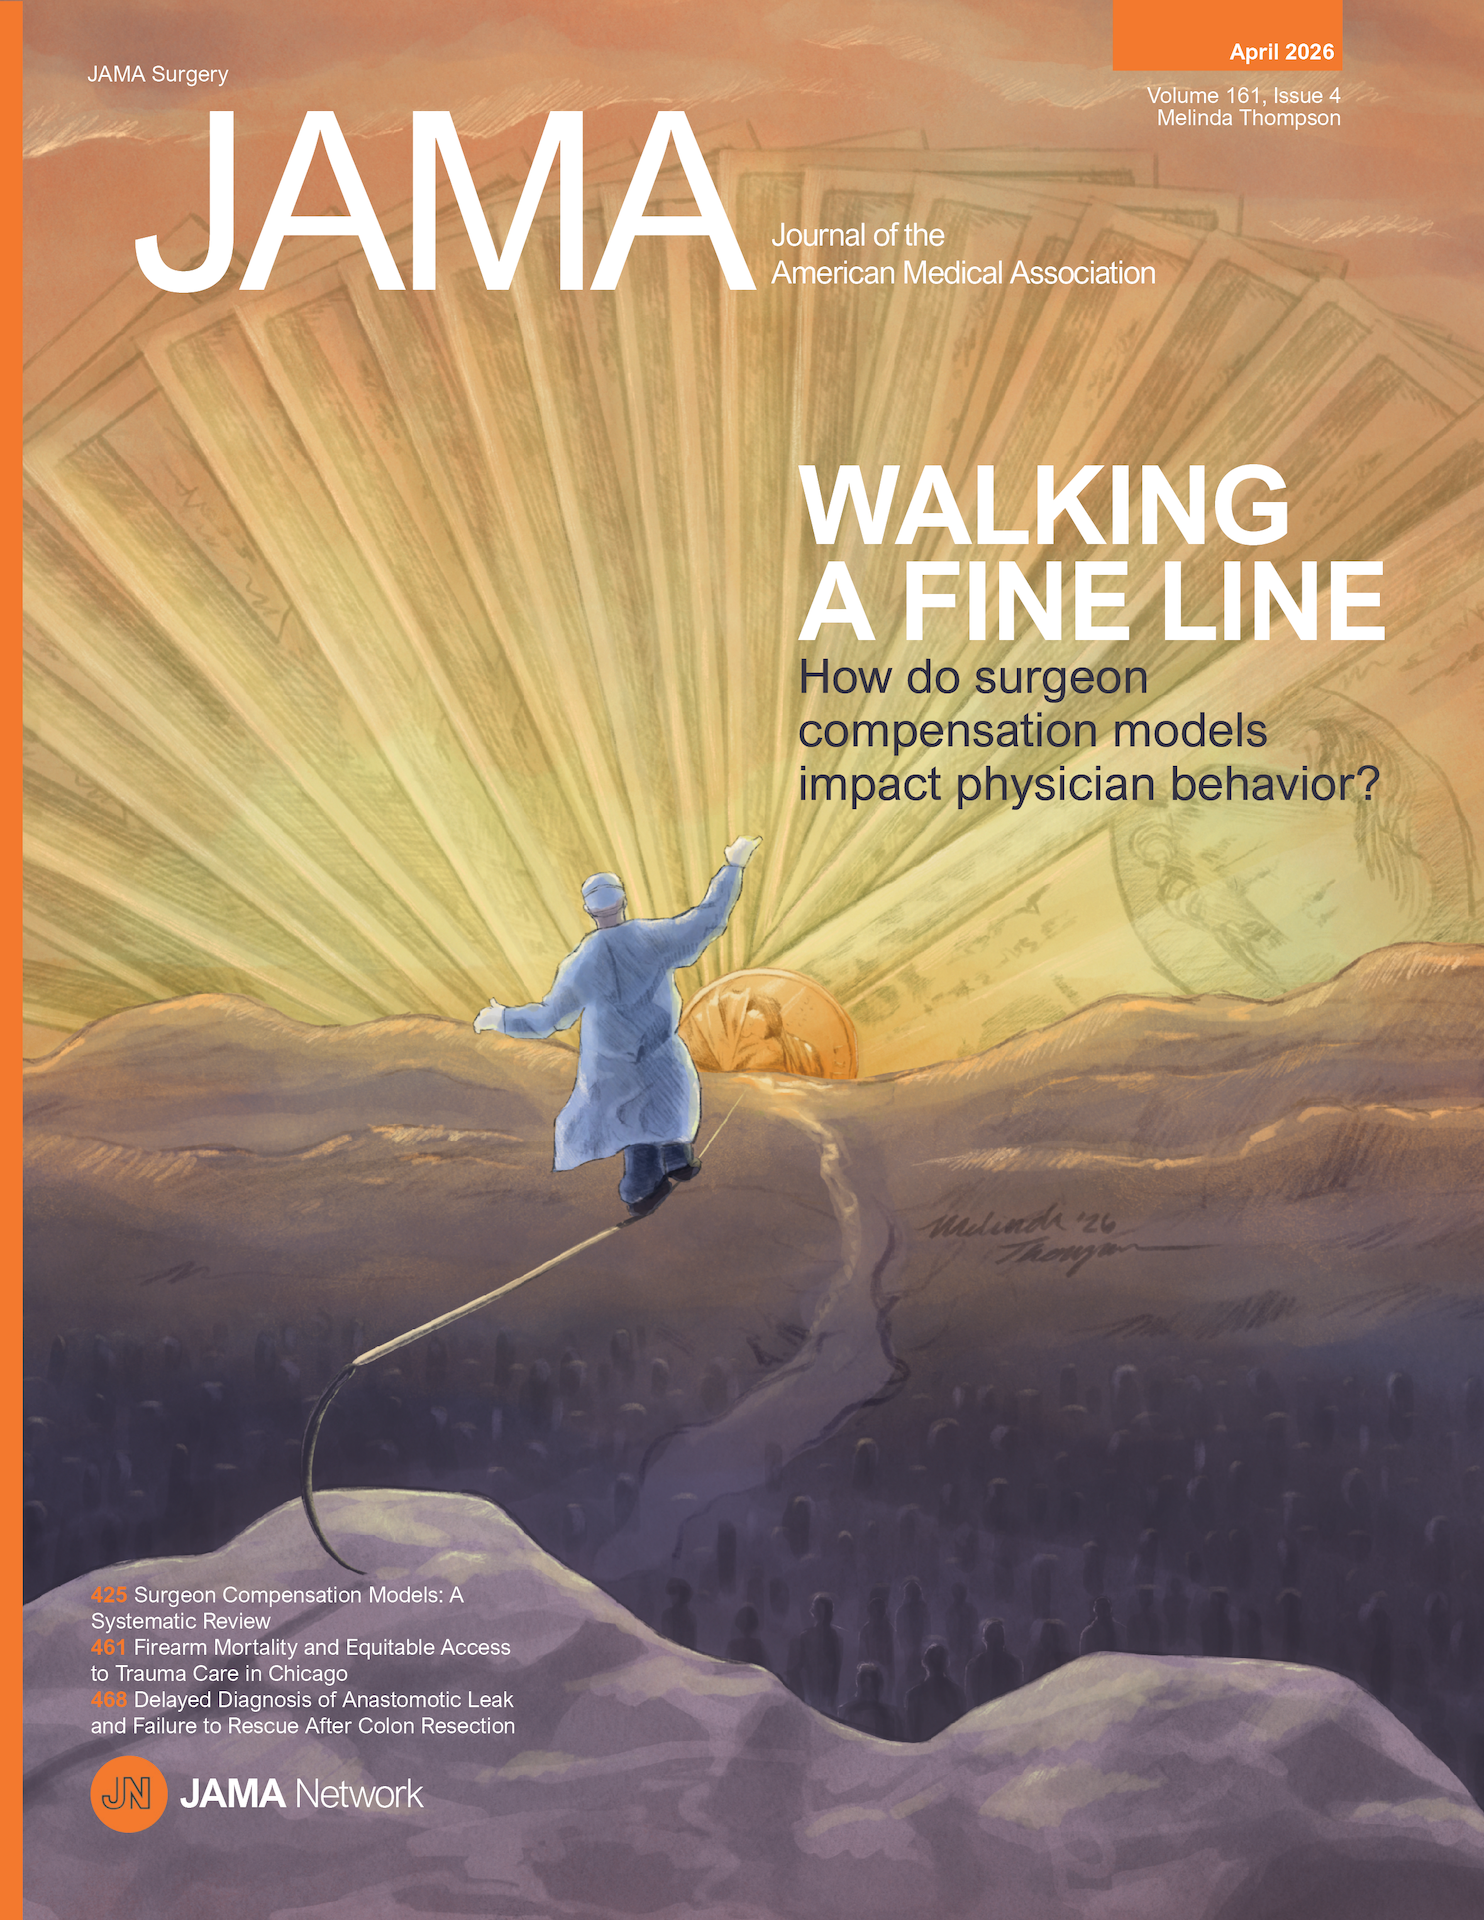

Editorial Journal Cover: Surgeon Compensation Models